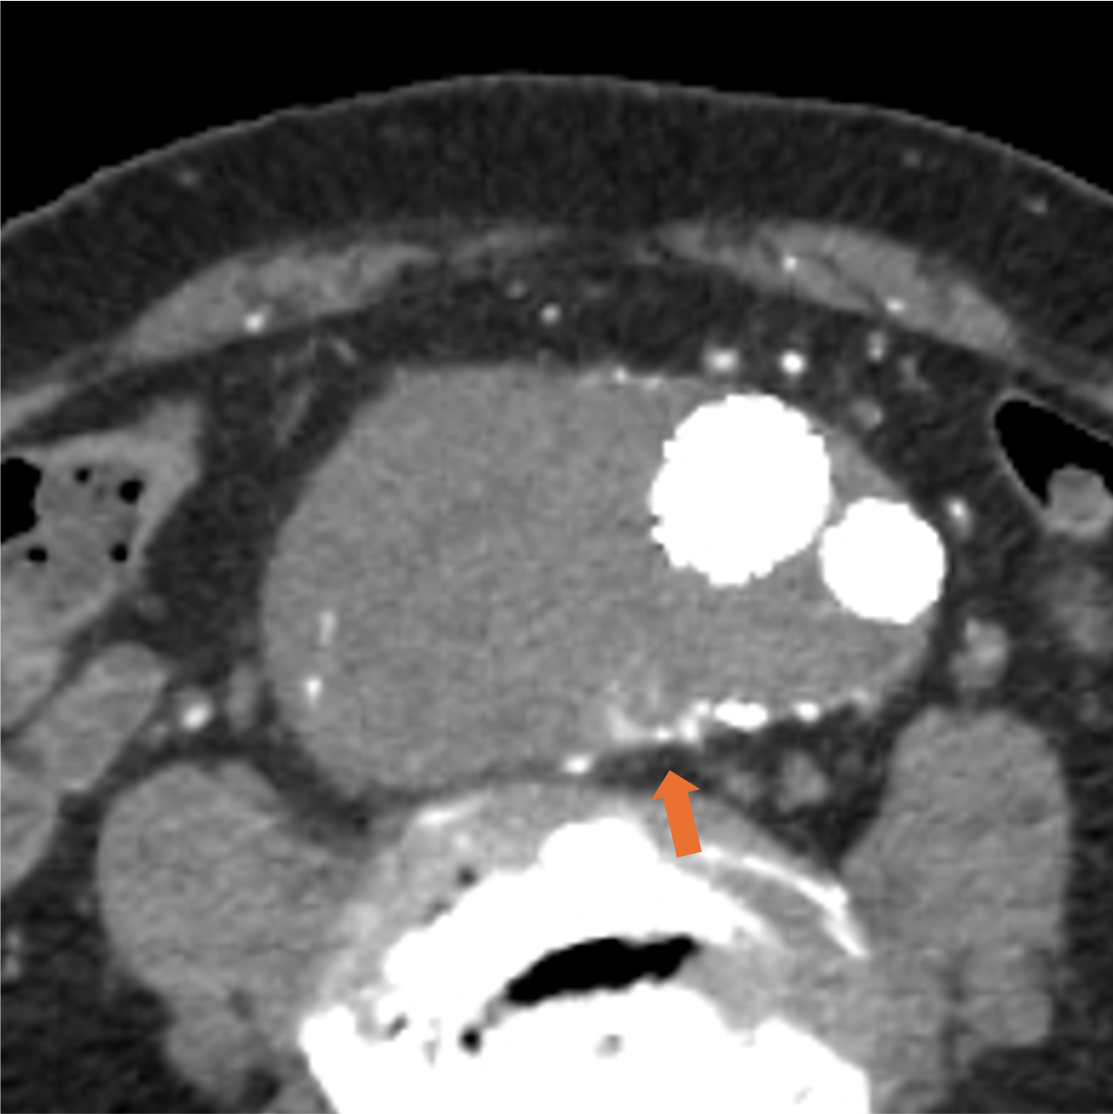

症例は80代男性。7年前に腹部大動脈瘤と右総腸骨動脈瘤に対しEVAR、2年前に腹部大動脈瘤のエンドリークに対し、下腸間膜動脈からコイル塞栓を行っている。動脈瘤が拡大傾向であったため、超音波検査が行われ、エンドリークが疑われた。評価と治療方針決定が必要と判断されたが、腎機能障害があったため入院での造影CTが計画された。

当該疾患の診断における造影CTの役割

CT技術や撮像プロトコル設定について

当院で使用されているCTは256列でのDual energy CTの撮影が可能なGEヘルスケア社のRevolution CTである。従来のSingle energy CTは1種類の管電圧を使用し、1種類のX線エネルギーを使用した撮像を行うが、本機種では高管電圧と低管電圧の2種類の異なる管電圧からそれぞれのX線エネルギーを使用した撮像が可能である。それにより、高画質かつ高コントラストの水密度画像とヨード密度画像が作成可能で、Deep learningを用いて解析を行うことでノイズの低減されたCT画像を再構成できる。本症例のようにTypeⅡエンドリークでは微小な血管が関与している場合があり、その検出と詳細な血管走行の確認において高コントラストかつ高画質の画像が求められ、Dual energy CTは有用である。